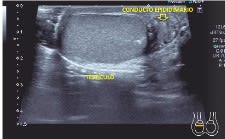

Aquí vas a encontrar una vía de entrada amable a esta maravillosa técnica, empezando por la parte menos entendible, como es la de los conceptos puramente físicos, después de una serie de protocolos habituales, incluido el Doppler, desmenuzados para que pueda resultarte de ayuda si tienes la suerte de poder empezar a hacer ecografía. Finalmente, unos capítulos de aproximación a técnicas cada vez más conocidas e implantadas en los centros de Salud, como son el contraste ecográfico y la elastografía.